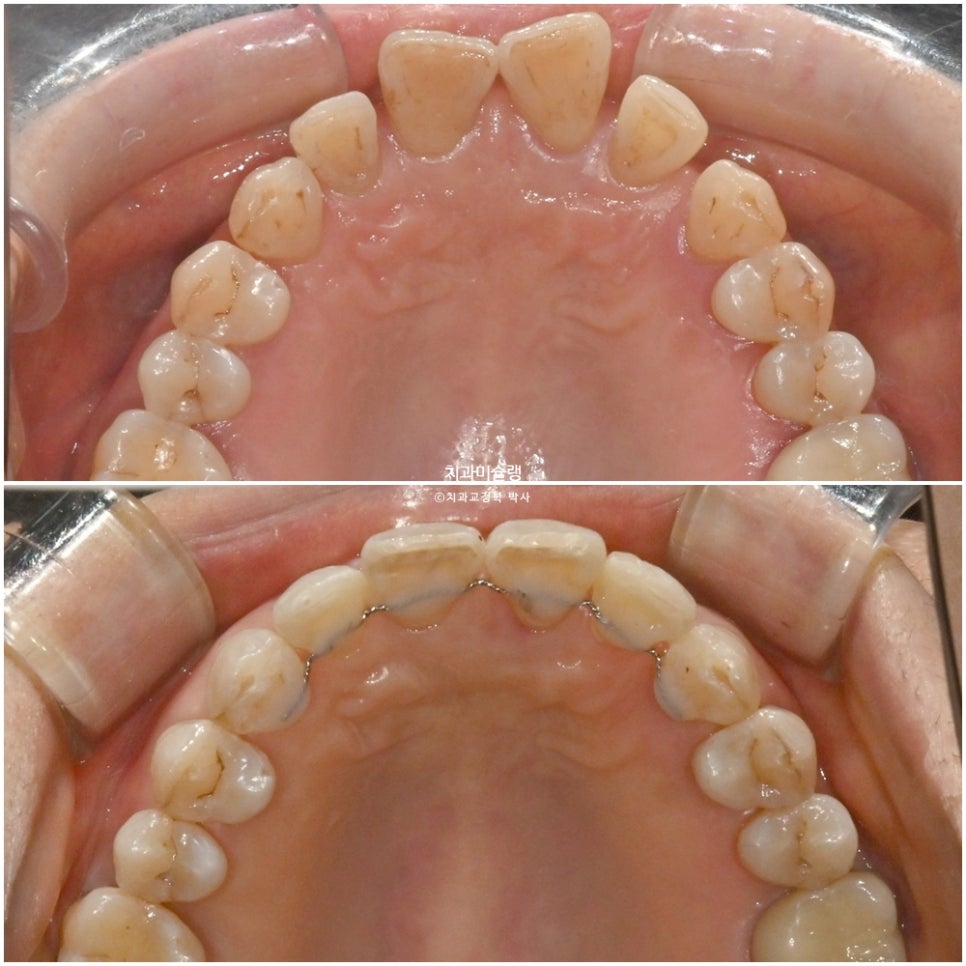

전악 잇몸치료를 하고 앞니 위주의 인비절라인 부분교정을 시작했습니다.

치료목표가 앞니 사이 벌어진 공간을 모두 없애는게 아니고 소량의 공간은 남기는 것이어서 인비절라인 익스프레스로 진행했습니다.

3월부터 6월까지, 7개 장치를 다 낀 후 모습입니다.

틈은 많이 줄었으나

앞니 회전이 아직 아쉽습니다.

2025년 2월, 치료를 마무리 했습니다.

총 치료기간은 11개월입니다.

어금니 교합은 그대로 유지되었으며 돌출되고 벌어진 앞니는 깔끔하게 제자리를 찾았습니다.

치료 전후 비교

앞니 부분교정이지만 한결 깔끔해진 미소가 돋보입니다.